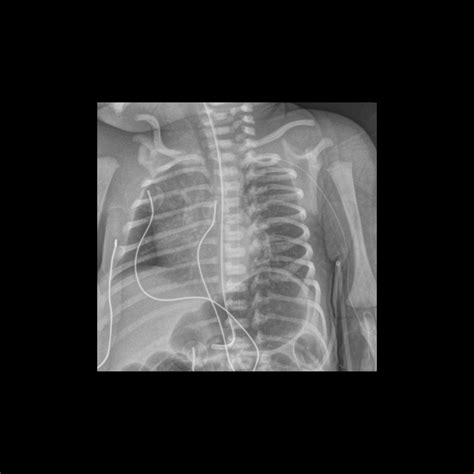

• X-rays: Often the first line of defense for bone fractures or lung issues.

X-ray Minimal Bone fractures, pneumonia, chest congestion

Furthermore, radiation sensitivity is a biological reality in younger patients. Because children have a longer life expectancy, the theoretical risk associated with cumulative radiation is handled with extreme caution. Specialized radiologists use dose-reduction software and settings tailored specifically to the body size of the patient, ensuring that the child receives the lowest effective dose of ionizing radiation possible.